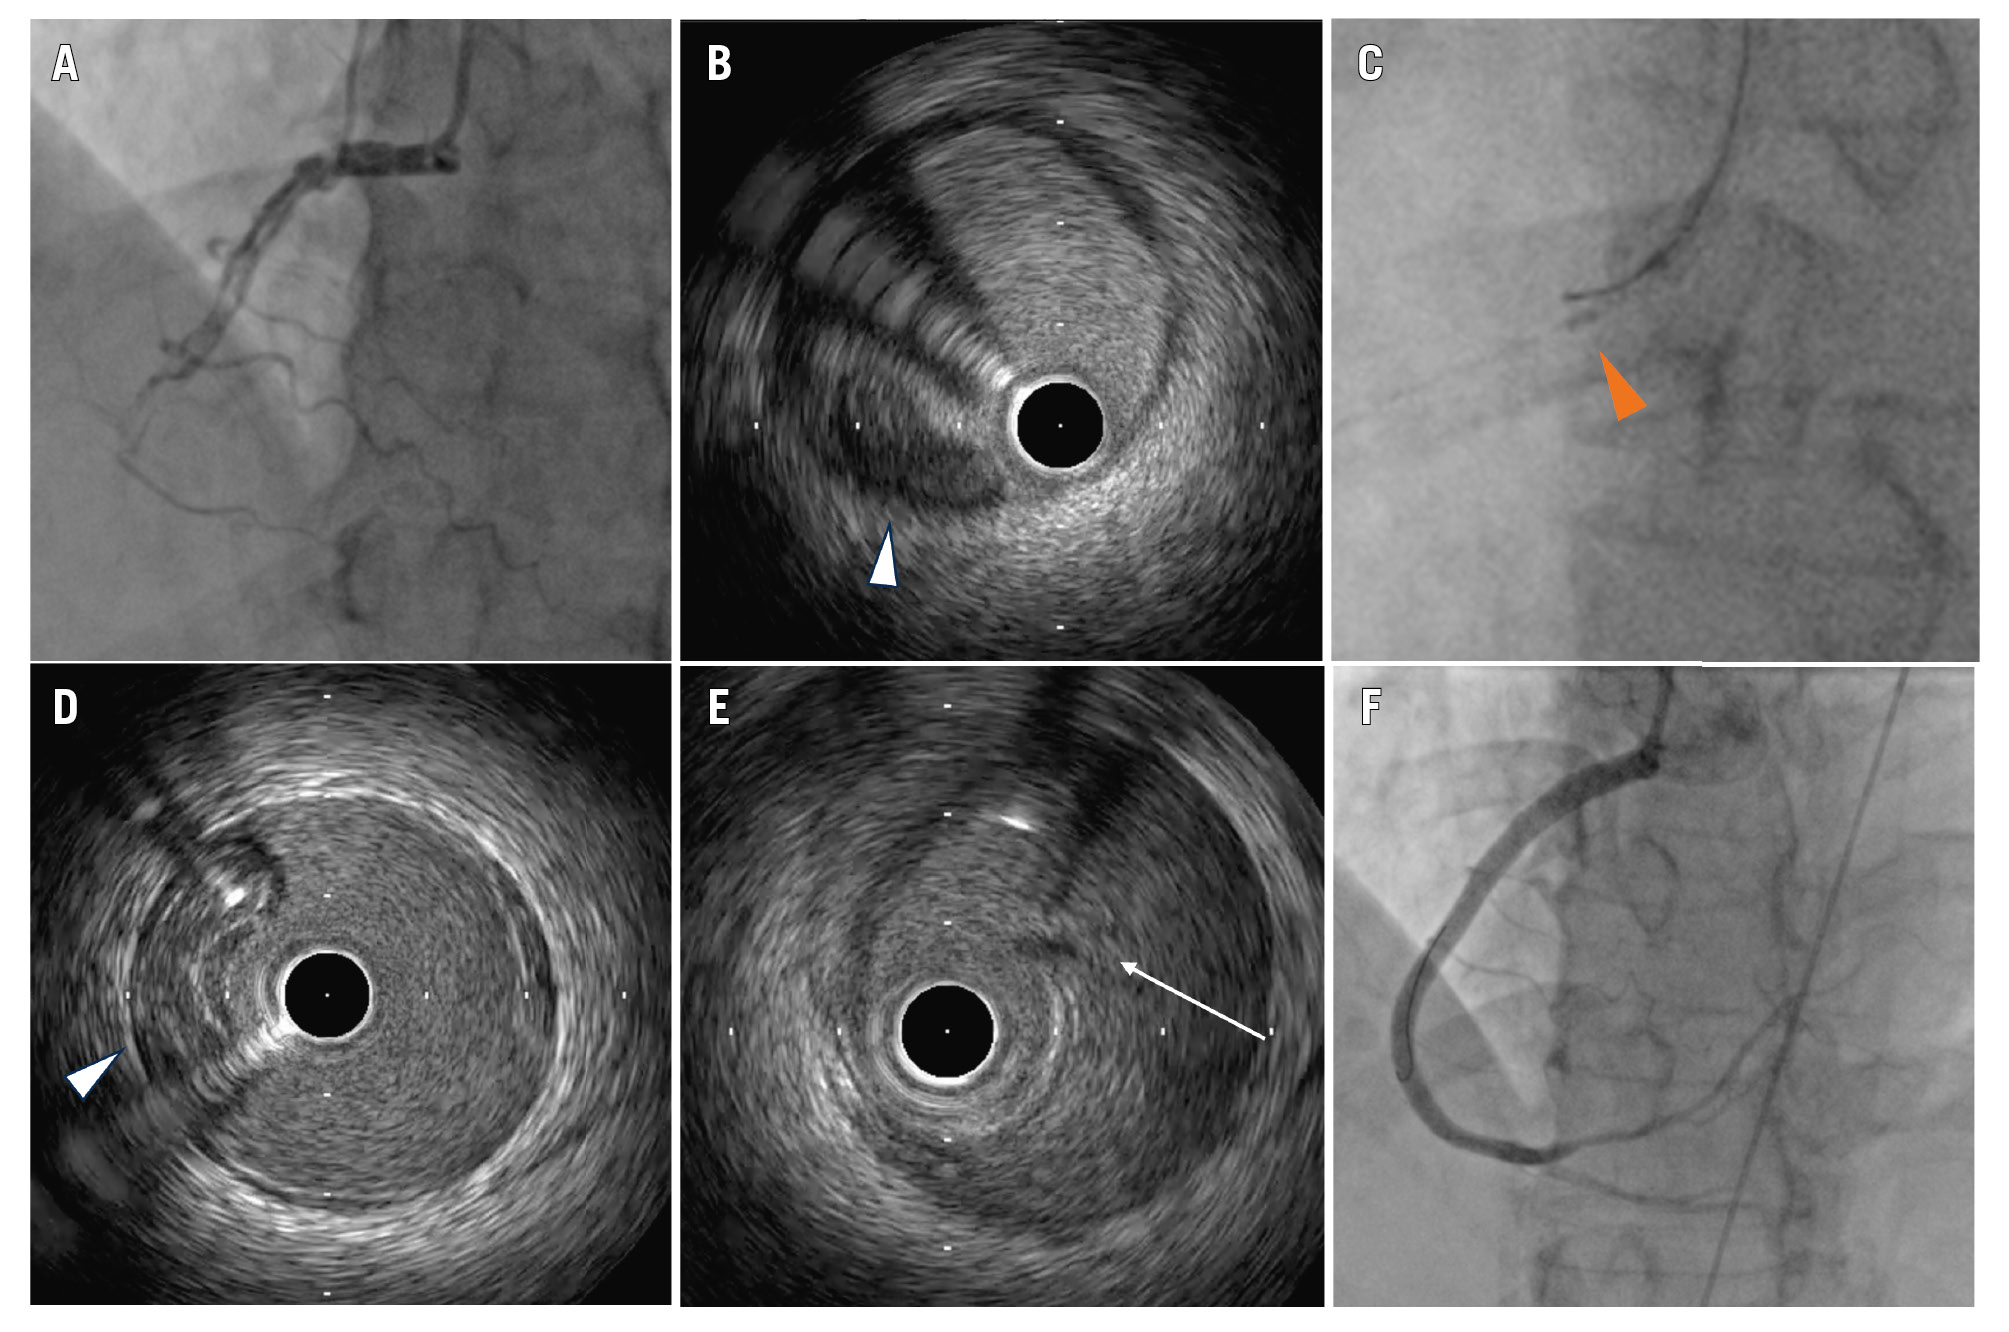

Coronary angiography showed spiral dissection arising from the ostial right coronary artery (RCA) with complete obstruction (Figure 1A). In view of haemodynamic compromise, percutaneous coronary intervention (PCI) was attempted. A Runthrough NS guidewire (Terumo) was passed into the distal RCA, but intravascular ultrasound (IVUS) showed that it was in the false lumen (Figure 1B). There was spontaneous coronary artery dissection (SCAD) arising from the ostial RCA with significant compression on the true lumen. Under real-time IVUS (AltaView [Terumo]) guidance, another Runthrough NS guidewire was passed into the true lumen successfully (Figure 1C, Figure 1D, Moving image 1). Cutting balloon angioplasty was performed (WOLVERINE [Boston Scientific]) to create fenestration between the true and false plane in order to re-establish coronary flow (Figure 1E). Drug-eluting stents were deployed from the ostial to distal RCA under IVUS guidance, covering the entire dissection segment (Figure 1F). The patient was able to wean off inotropic support and was discharged on post-op day 5.

Figure 1. IVUS-guided wiring in a patient with SCAD. A) Baseline angiogram showing ostial RCA SCAD. B) IVUS image of SCAD showing a compressed true lumen (white arrowhead). C) Fluoroscopic image of real-time IVUS-guided wiring (orange arrowhead: IVUS probe). D) IVUS confirmed true luminal wiring (white arrowhead). E) IVUS image after cutting balloon angioplasty showing fenestration of the dissection flap (white arrow). F) Final angiographic result. IVUS: intravascular ultrasound; RCA: right coronary artery; SCAD: spontaneous coronary artery dissection